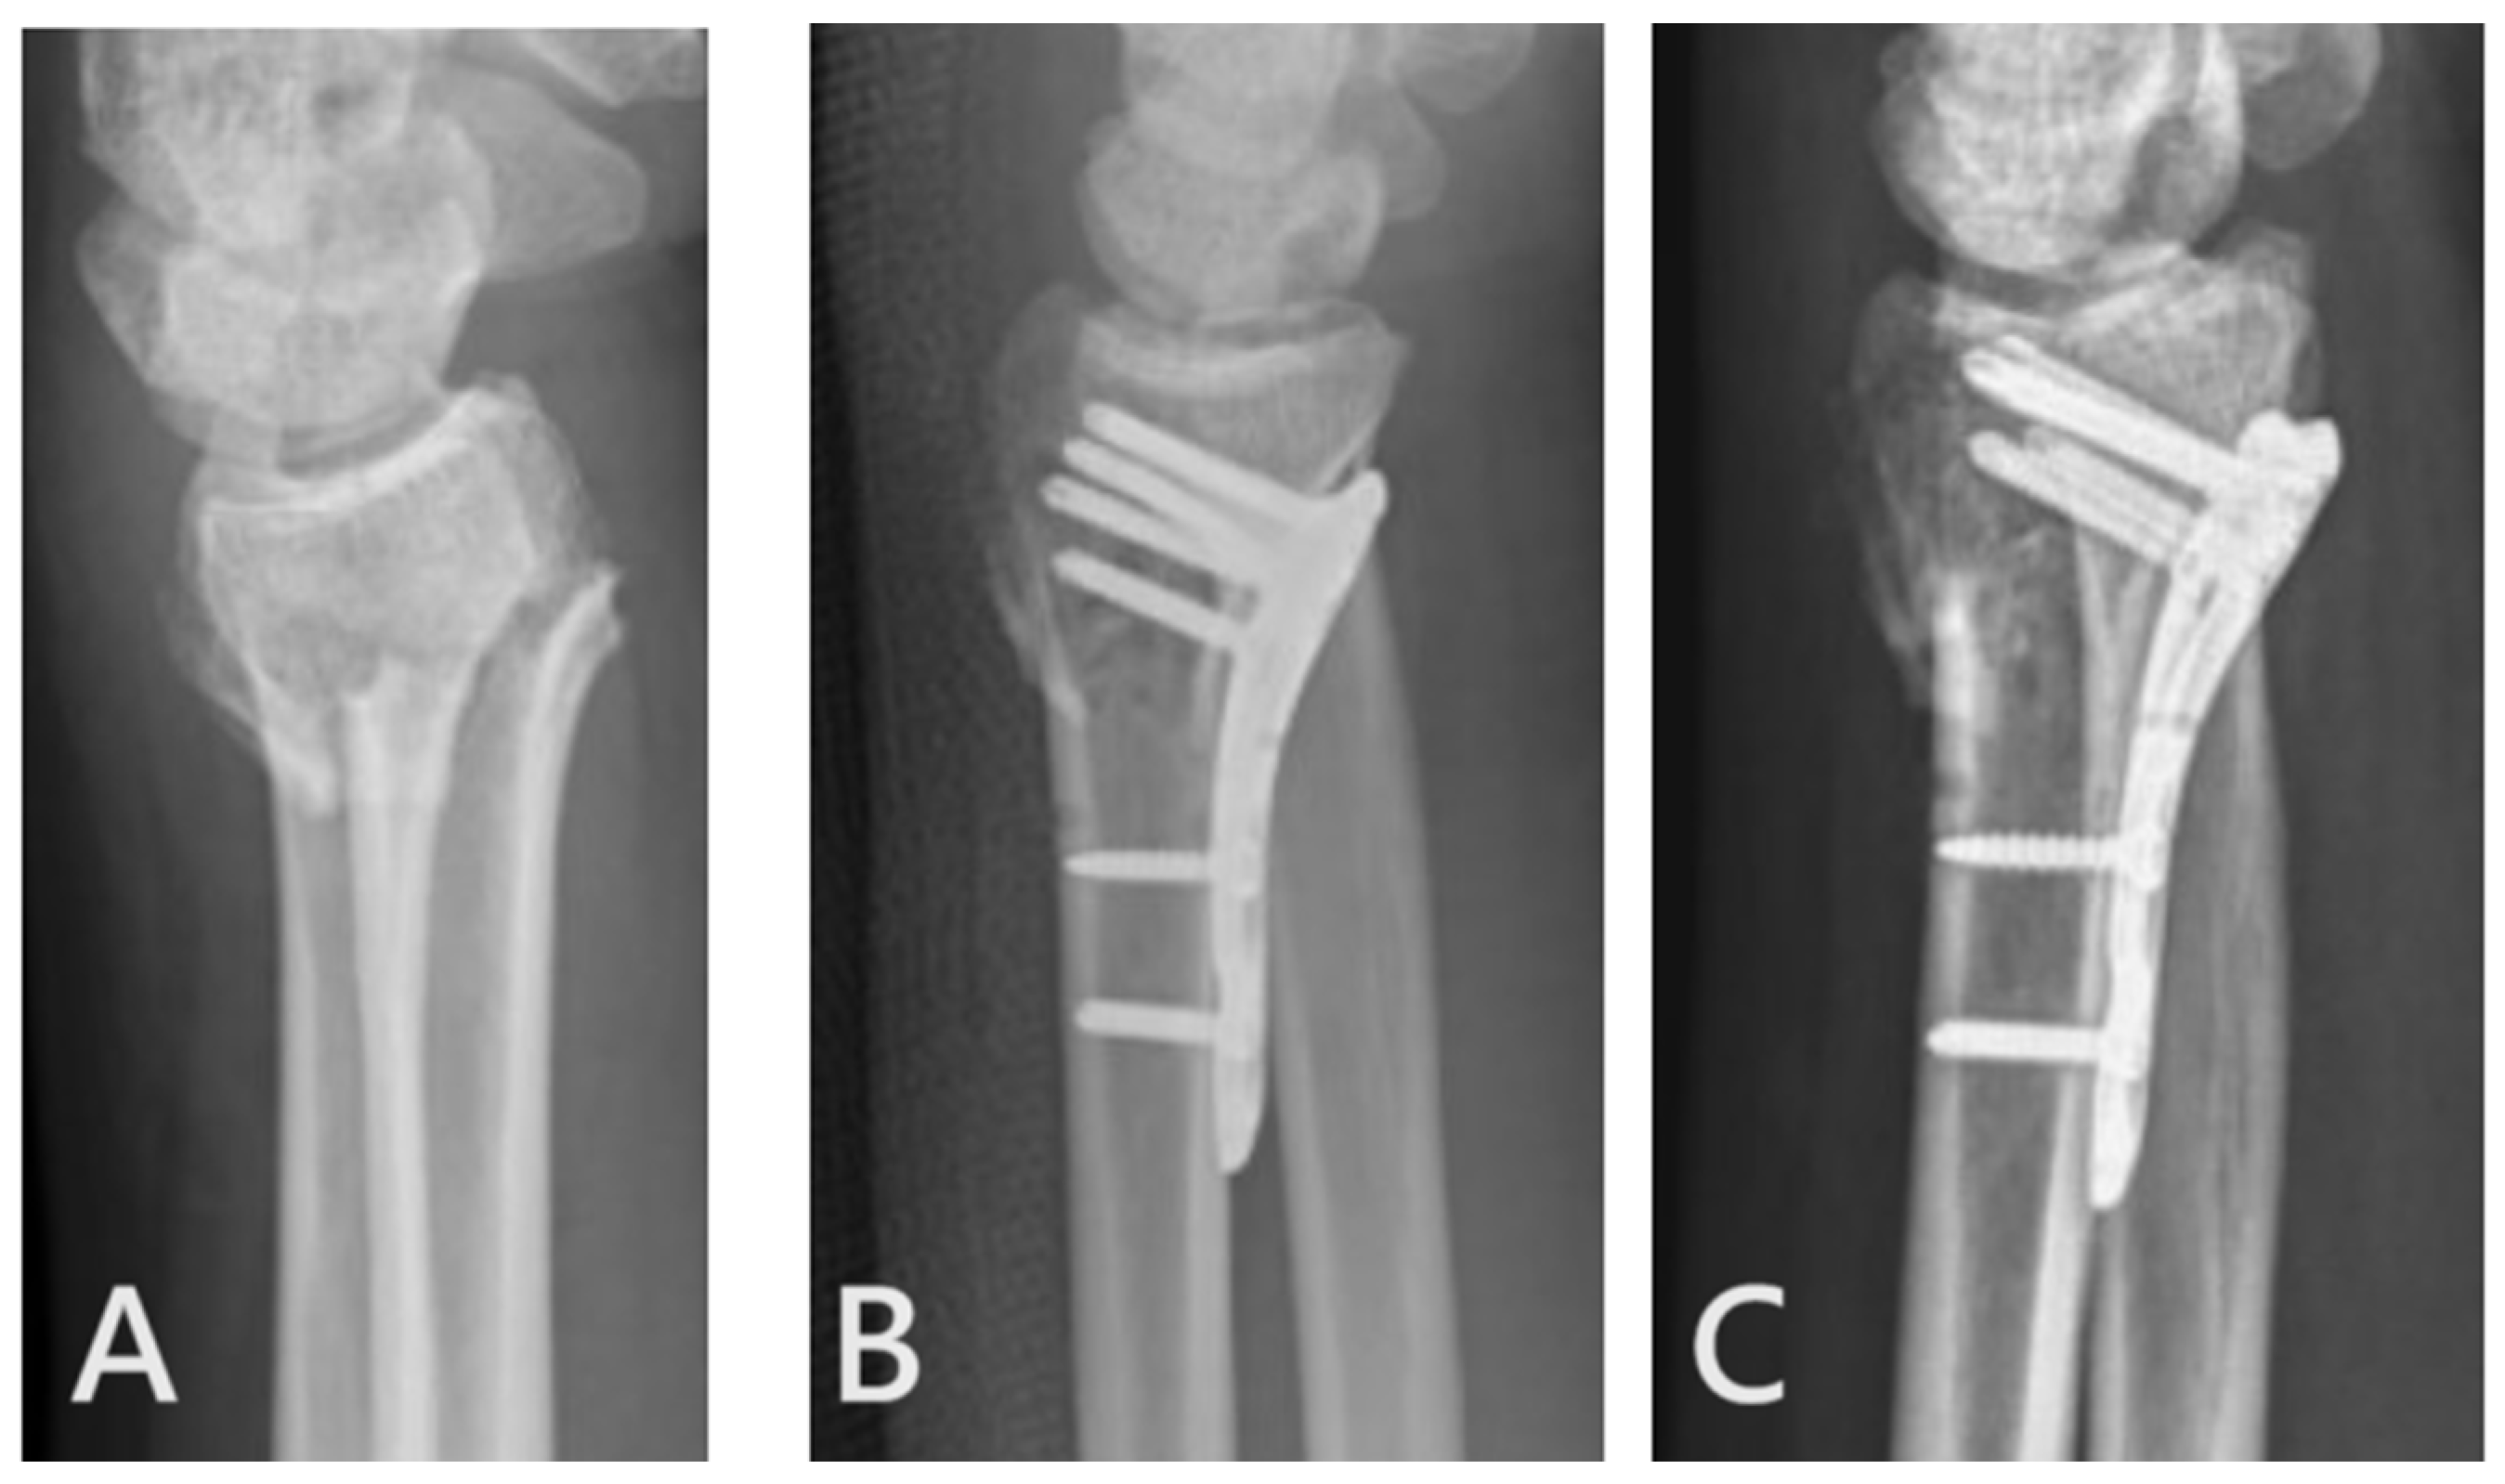

2.2. Surgical Techniques of Ultimate Incision Surgery

2.3. Surgical Techniques of Conventional Incision Surgery